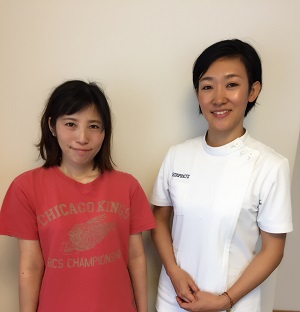

施術前

施術後

副院長の椎間板ヘルニア(4ヶ月後)※効果には個人差があります